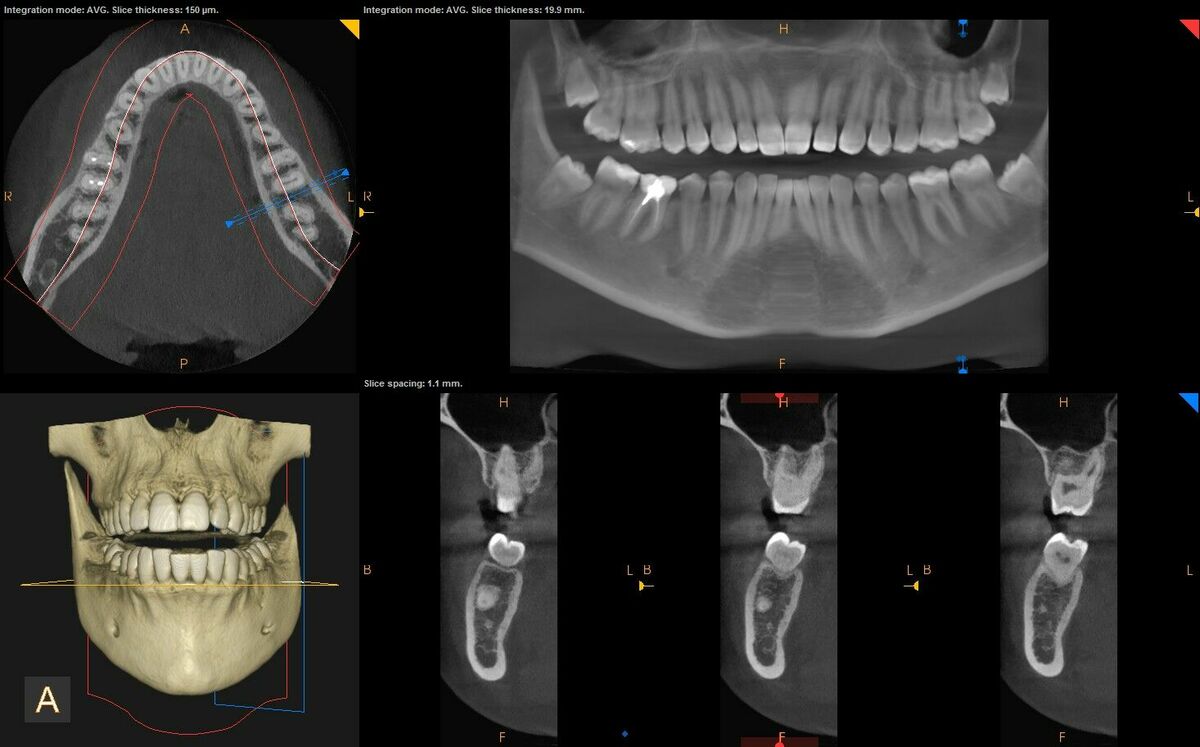

3 D rentgens

arde dental